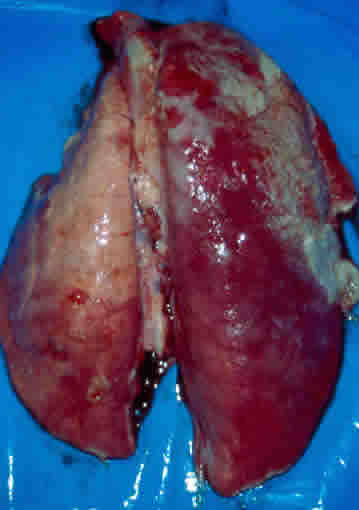

. Cavité thoracique : péricardite fibrineuse, pleurésie fibrineuse (pas d'œdème pulmonaire).

Poumons

avec dépôts de fibrine

Poumons

avec dépôts de fibrine

| Cavité thoracique | Poumons

: hépatisation rouge diffuse Cœur : normal |

Poumons

: pleurésie fibrineuse, hépatisation grise (14/28) Cœur : péricardite fibrineuse |